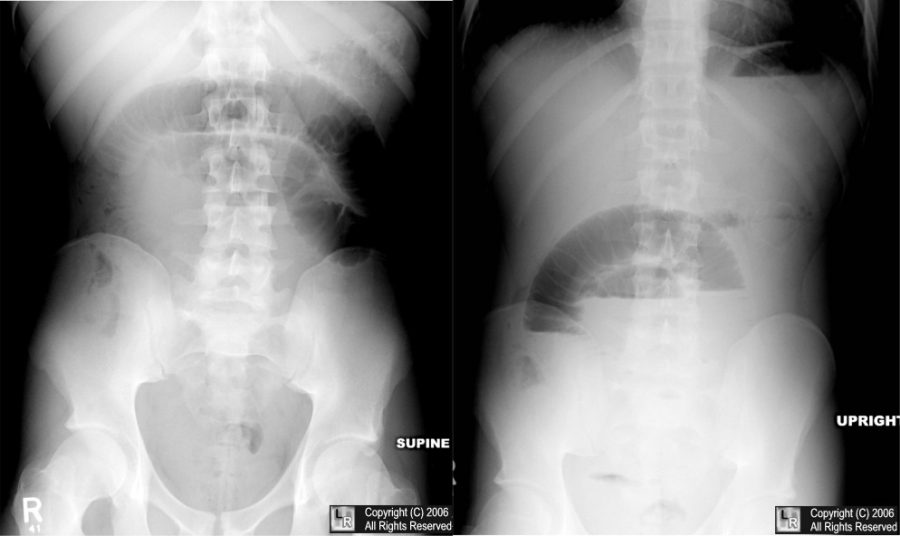

Labeled Kub X Ray Anatomy . Doctors can use it to help them. this article lists a series of labeled imaging anatomy cases by body region and modality. this involves assessment of the bowel gas pattern, soft tissue structures, and bones. This view is useful in assessing abdominal pathologies, including bowel obstructions, calcifications and neoplastic changes. Full assessment includes a check of.

This view is useful in assessing abdominal pathologies, including bowel obstructions, calcifications and neoplastic changes. this article lists a series of labeled imaging anatomy cases by body region and modality. this involves assessment of the bowel gas pattern, soft tissue structures, and bones. Doctors can use it to help them. Full assessment includes a check of.